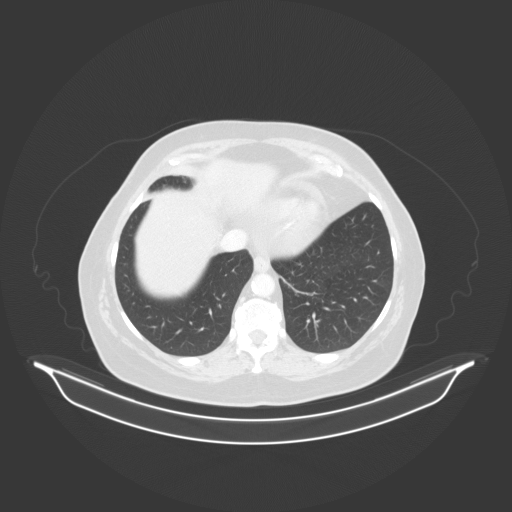

Image Grid

4Γ—3 grid: Rows show different image types (Original NATIVE, Reconstructed NATIVE, Original VENOUS, Generated VENOUS), Columns show windowing techniques (No Window, Lung Window, Mediastinum Window)

Lung window (WL -600, WW 1500 β†’ Low βˆ’1350, High +150)